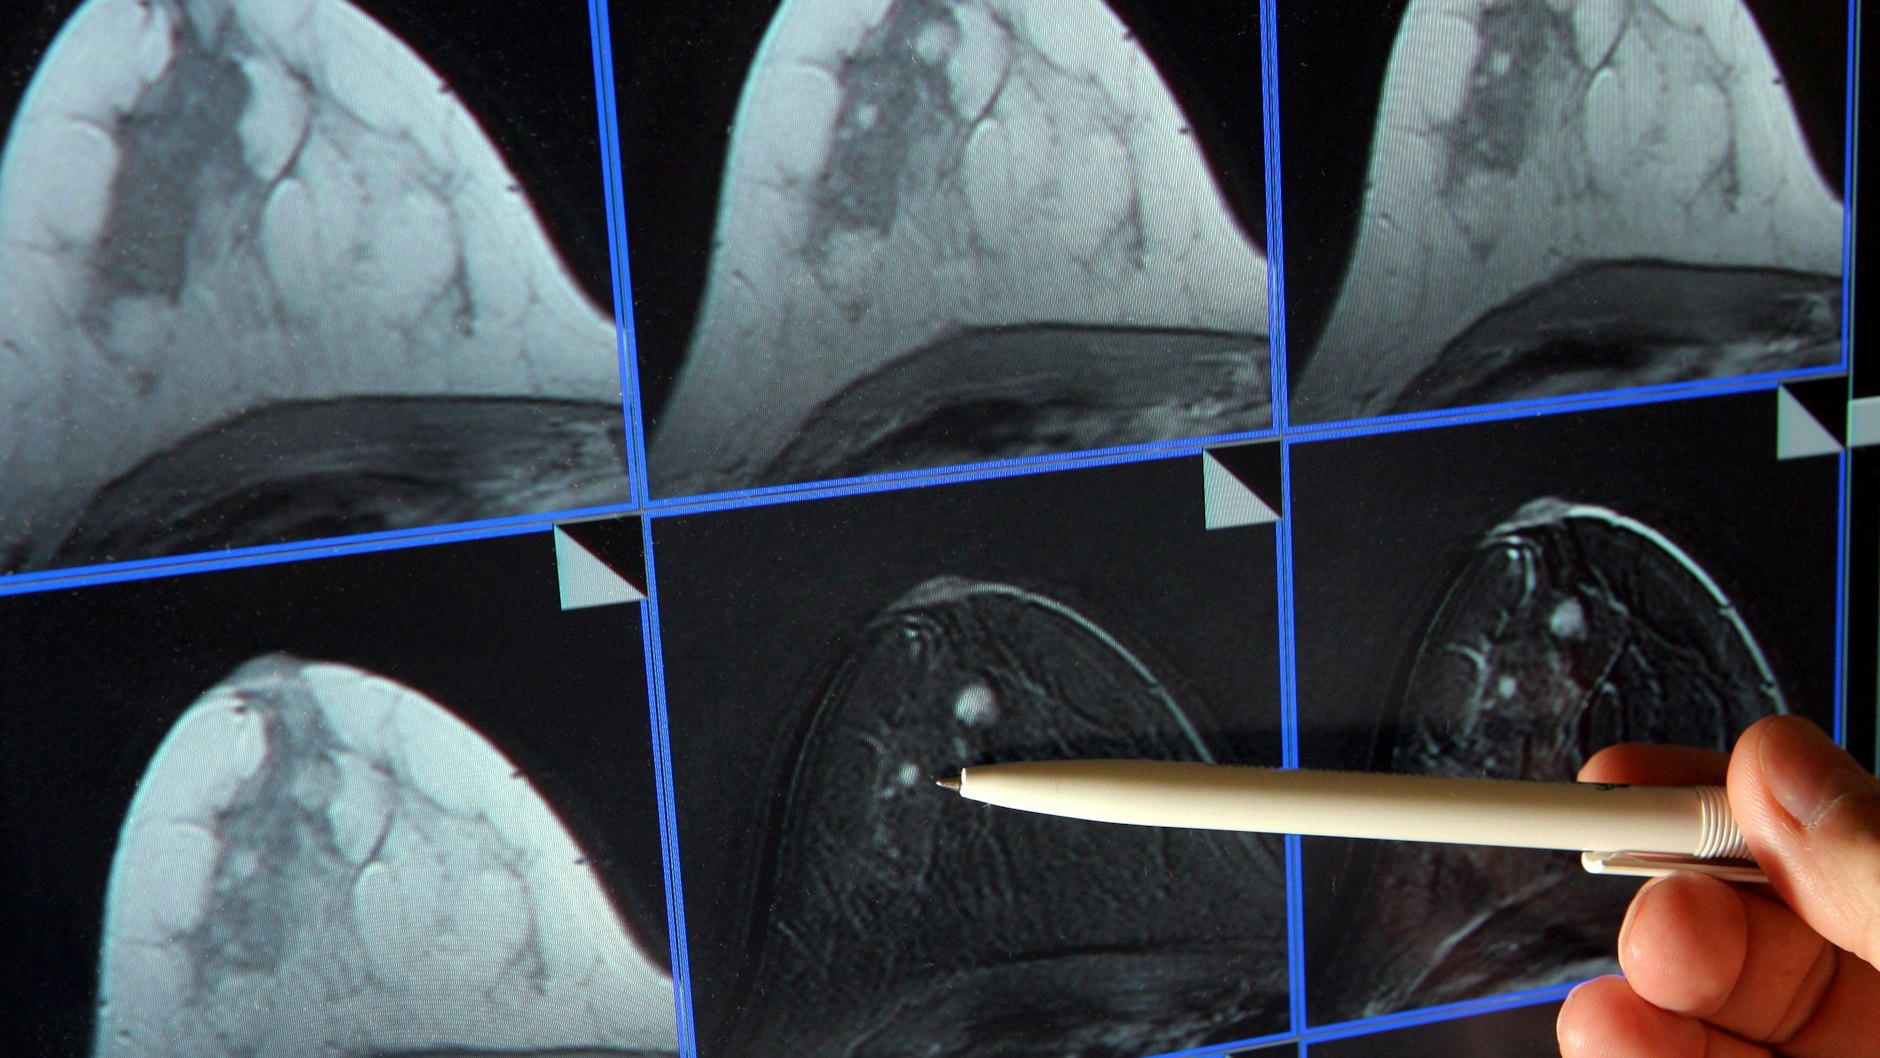

Tamoxifen wird in der Nachsorge eingesetzt - Ziel ist es, langfristig die Wahrscheinlichkeit eines Rückfalls zu senken. „Es ist unverzichtbarer Bestandteil der Therapie von Patient*innen mit Hormonrezeptor-positivem Mammakarzinom“, heißt es in einer Stellungnahme, mit der fünf Fachgesellschaften gemeinsam auf die Situation reagiert haben.